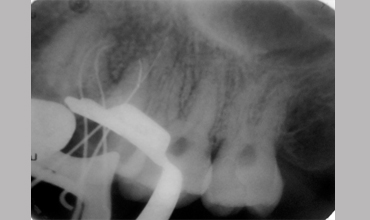

MB2

Management Of Maxillary First Molar With Mb 2 Canal